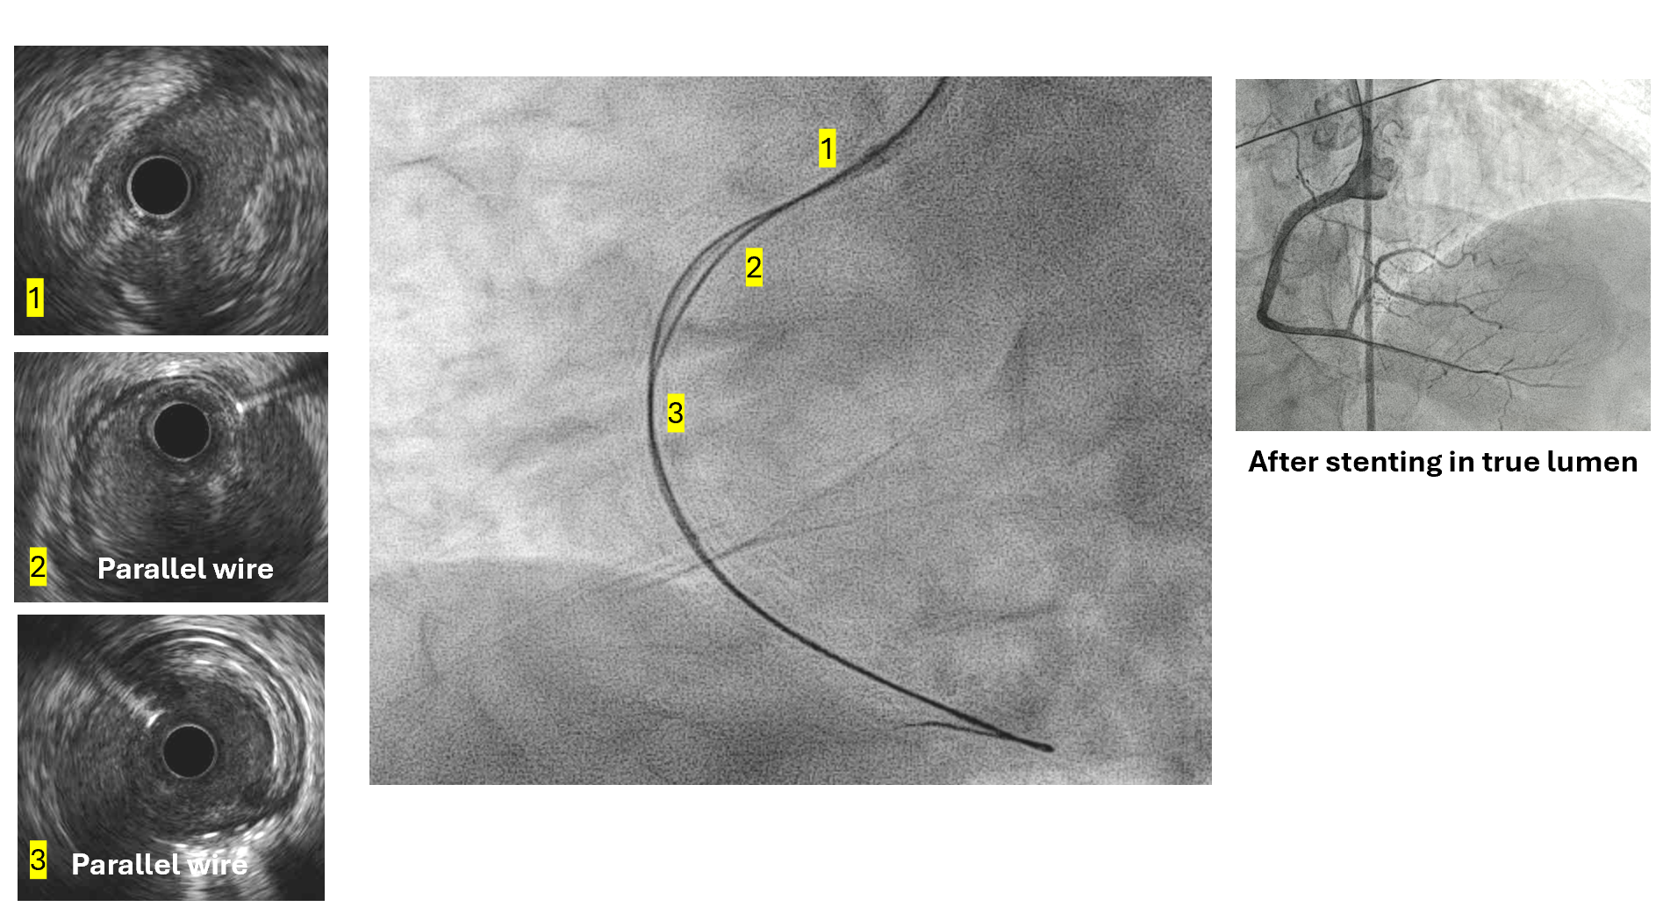

The SAL1 guiding catheter was unstable, jumping in and out the ostium. We deployed PK Papyrus 2.5 x 20 mm stent graft to dRCA quickly and planned to deployed another DES to p-dRCA. However, the patient agitated and the whole system was removed, leaving severe spiral dissection, starting from the ostium to middle RCA.We tried to wire FC, XTA and sion balck to true lumen but fail. Switched to 6F JR guiding but still fail.We wired FC to distal RCA with parallel wire technique and checked IVUS. The distal wire was over true lumen, but false lumen wiring was noted since proximal RCA.We wired XTA to true lumen under IVUS image. Then true lumen wiring was completed.We dilated with 1.5 balloon. Followed by Ryurei 2.50 x 15 mm to mRCA.We deployed Ultimaster Tansei 3.00 x 38 mm and Ultimaster Tansei 4.00 x 18 mm to p-dRCA.Post-dilated with 3.0, 3.5, and 4.0 NC balloon to RCA.The final IVUS showed well stent expansion.The final flow is good. We closed the procedure smoothly.